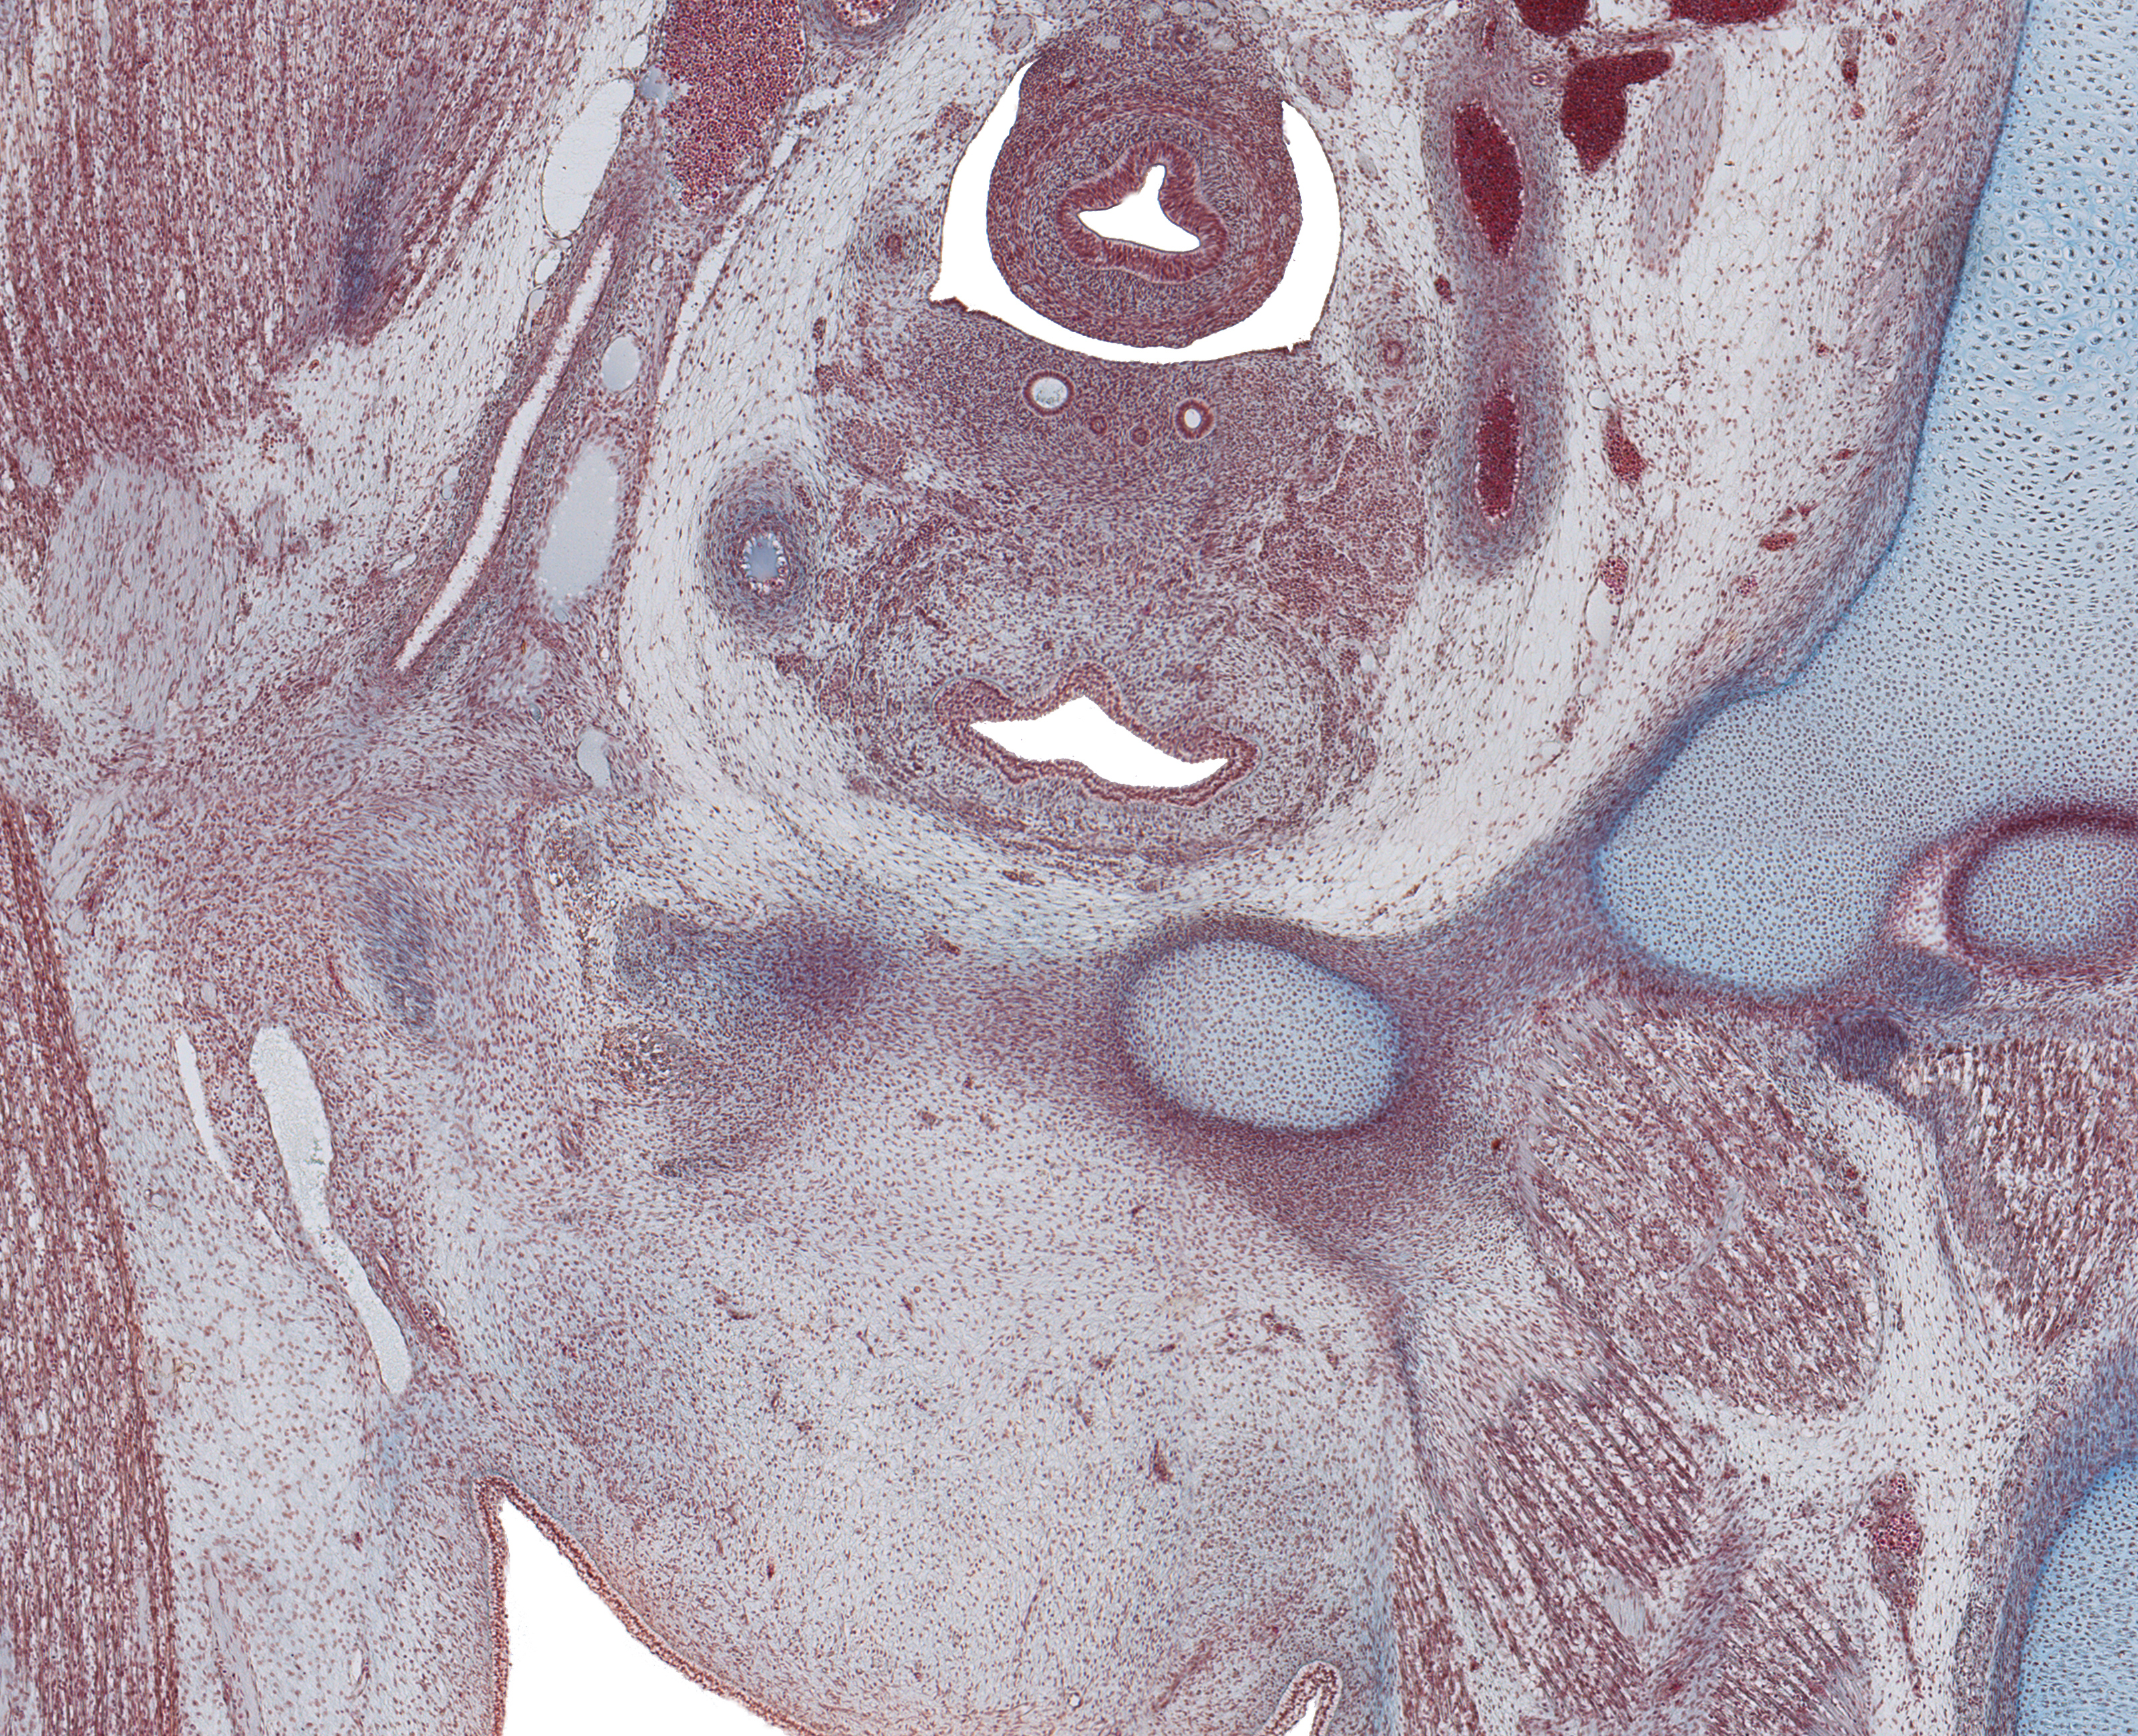

Tissue

Paramesenephric Ducts, and Gubernaculum Testis in Scrotal Fold

Carnegie Embryo #9226

193-01-01